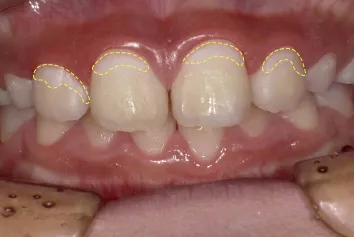

写真1 黄色の破線がむし歯の始まり

写真1の歯はむし歯の始まりを示しています。歯の表面が白く濁っており、エナメル質の結晶が溶け出しているのです。歯に穴があく一歩手前の状態です。